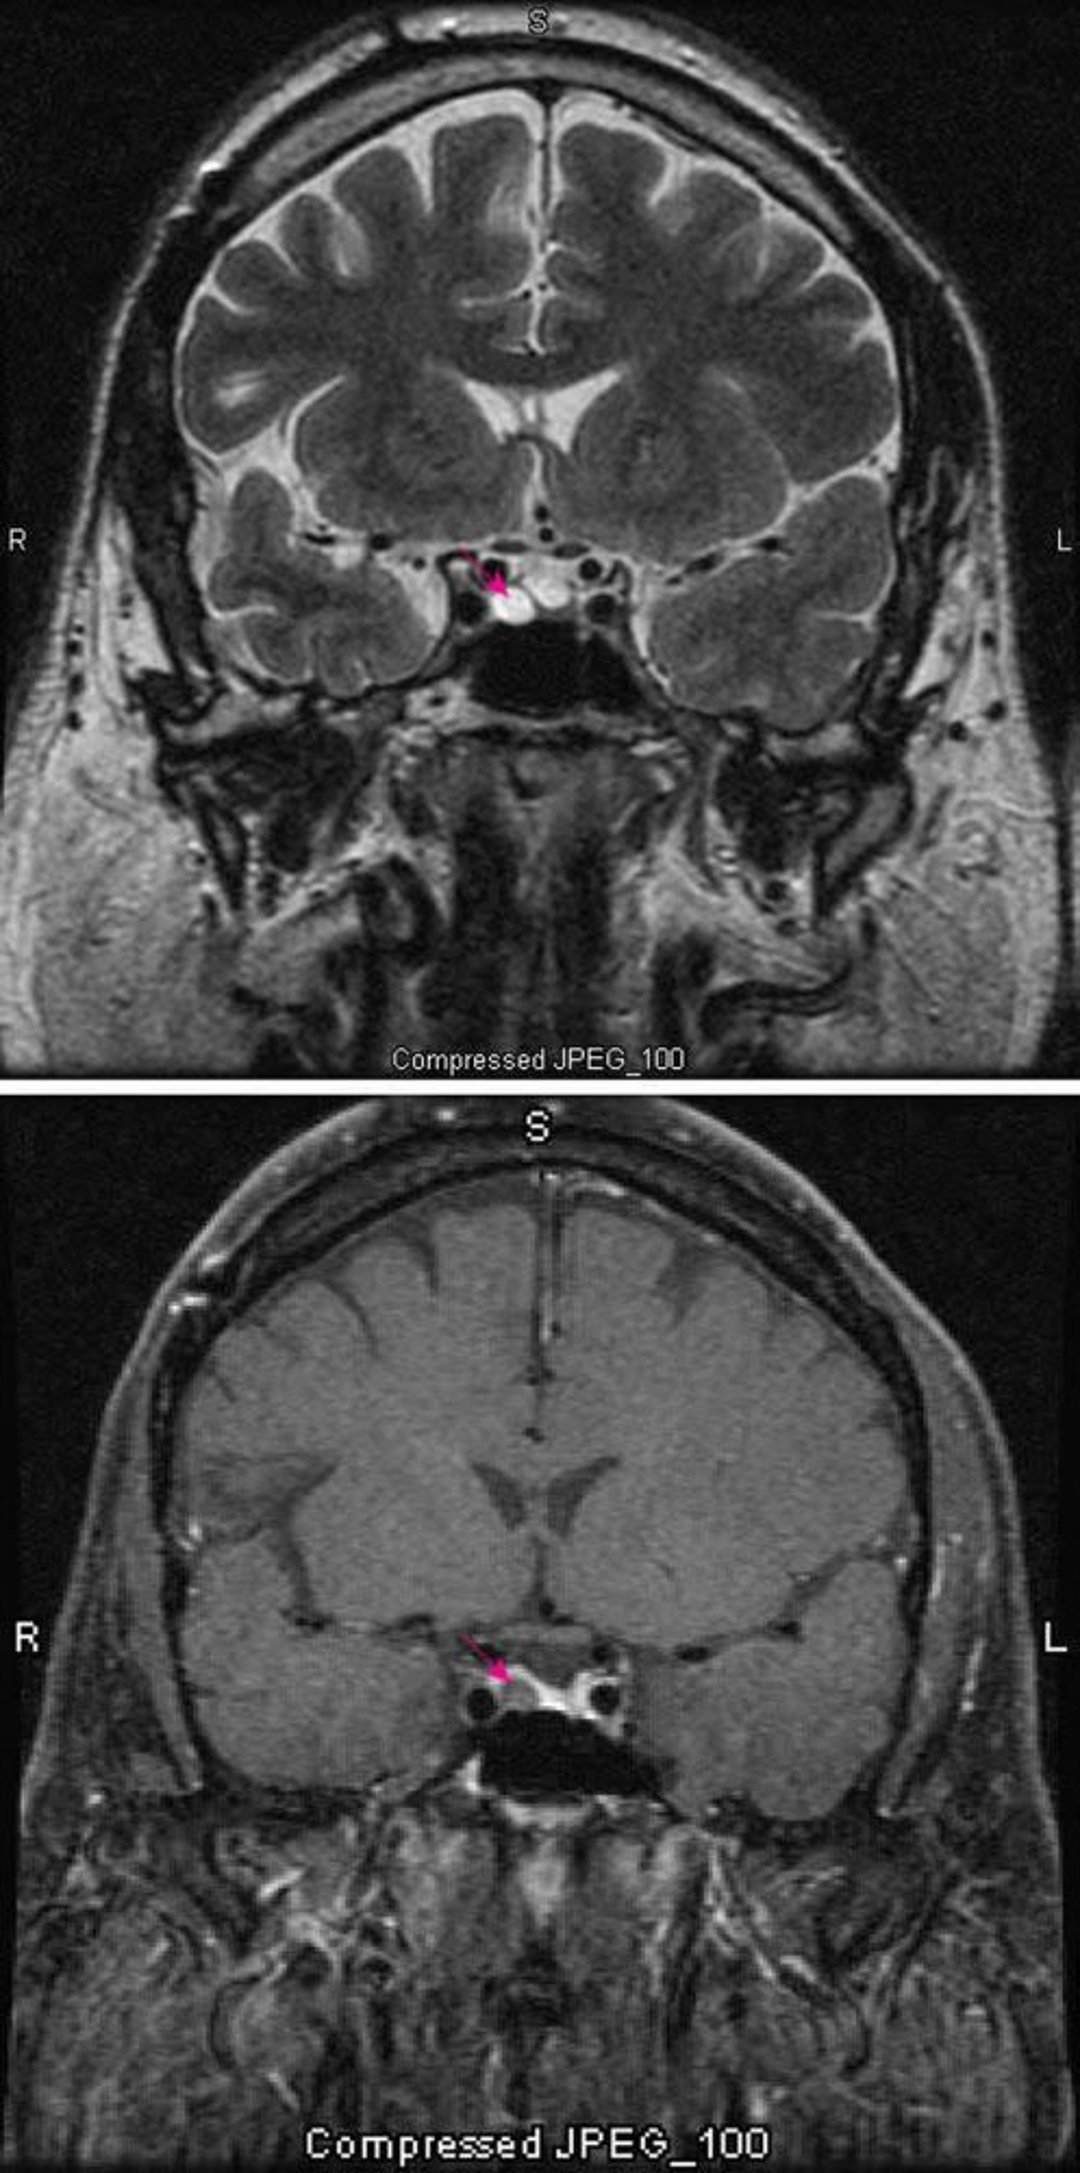

Microadenoma hipofisário

RM ponderada em T2 (parte superior) mostra microadenoma hipofisário (seta vermelha). A hipófise normalmente capta o contraste (seta vermelha). O adenoma parece mais claro.

Imagens cortesia de William R. Shapiro, MD.